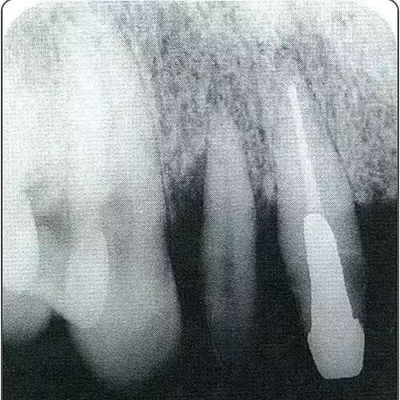

深牙周袋的治療

圖10-10  術后2年的x片。確認骨水平獲得改善,牙周探診值在2mm以下